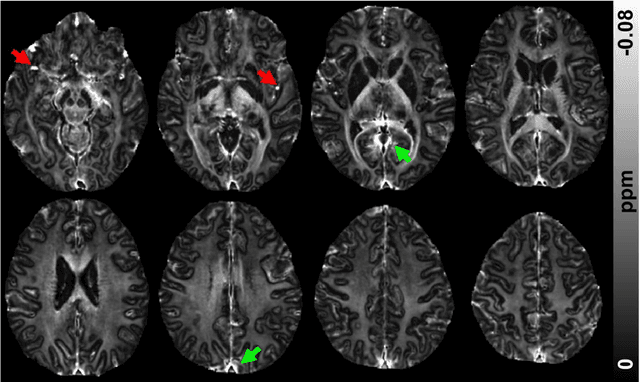

Abstract:In MRI, researchers have long endeavored to effectively visualize myelin distribution in the brain, a pursuit with significant implications for both scientific research and clinical applications. Over time, various methods such as myelin water imaging, magnetization transfer imaging, and relaxometric imaging have been developed, each carrying distinct advantages and limitations. Recently, an innovative technique named as magnetic susceptibility source separation has emerged, introducing a novel surrogate biomarker for myelin in the form of a diamagnetic susceptibility map. This paper comprehensively reviews this cutting-edge method, providing the fundamental concepts of magnetic susceptibility, susceptibility imaging, and the validation of the diamagnetic susceptibility map as a myelin biomarker. Additionally, the paper explores essential aspects of data acquisition and processing, offering practical insights for readers. A comparison with established myelin imaging methods is also presented, and both current and prospective clinical and scientific applications are discussed to provide a holistic understanding of the technique. This work aims to serve as a foundational resource for newcomers entering this dynamic and rapidly expanding field.